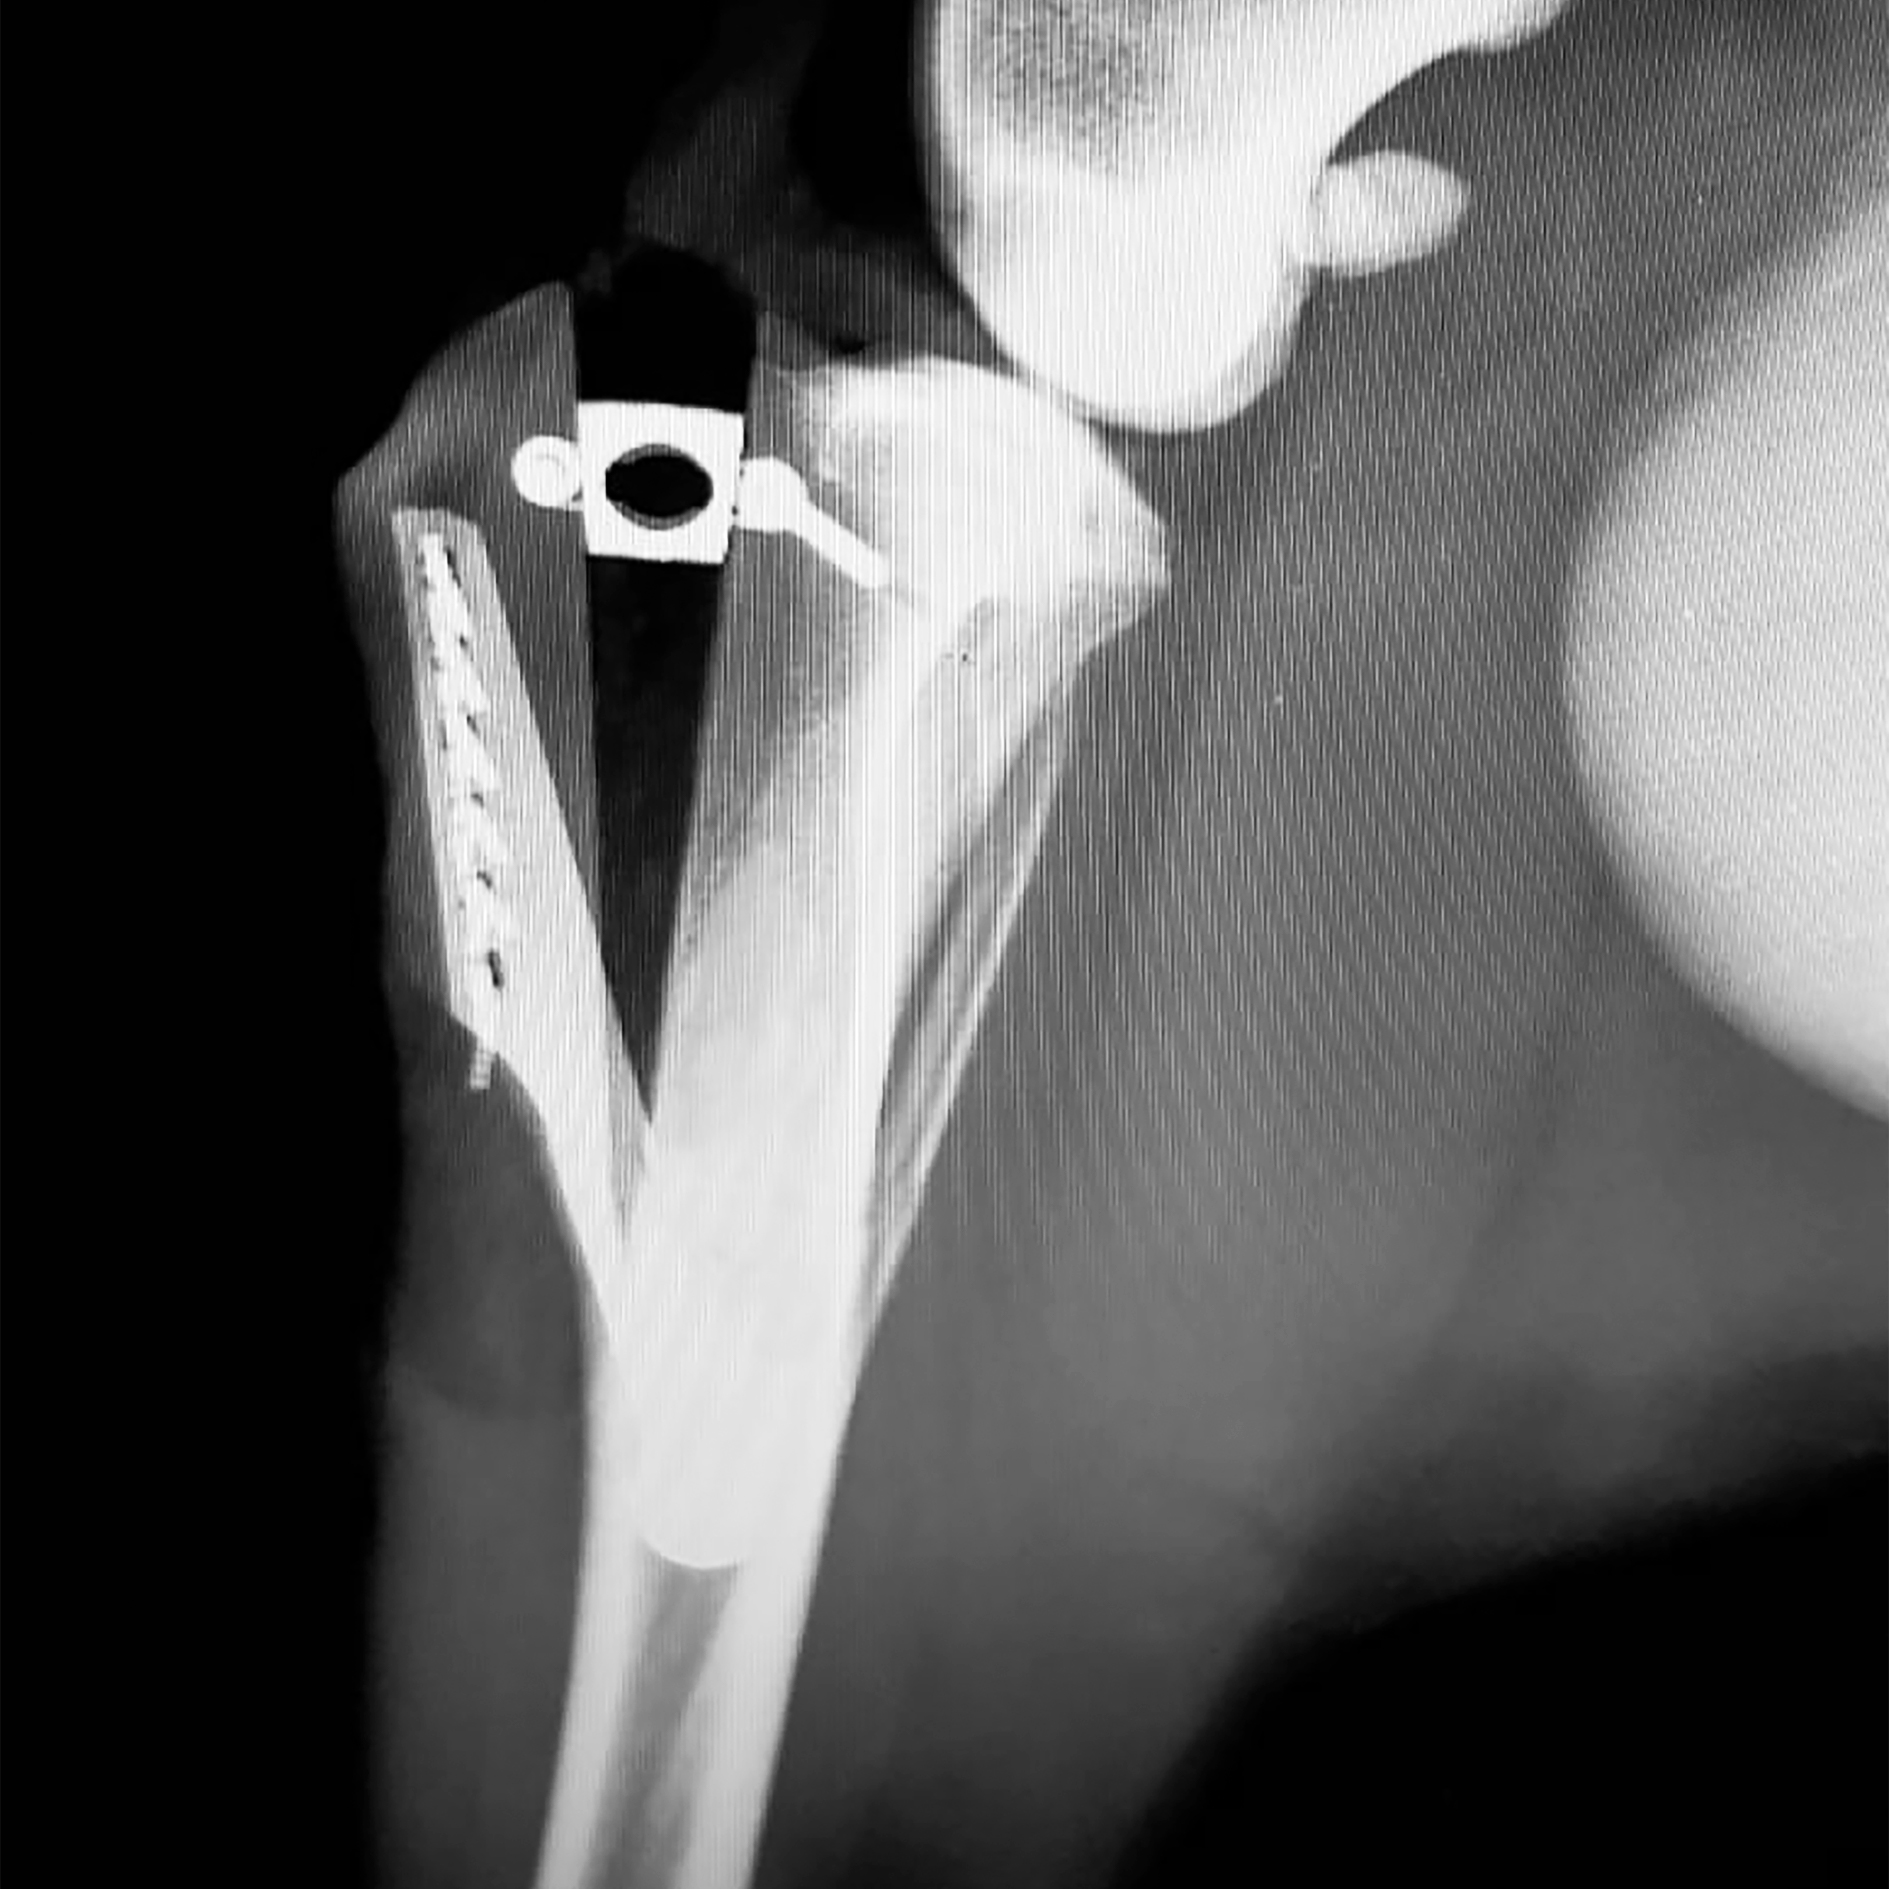

TTA RAPID® Technique: An innovation over the standard TTA, the TTA RAPID® Technique is designed to be a faster and simplified procedure by using a specialized 3D-printed Titanium cage implant, which eliminates the need of a separate metal plate. It’s unique design allows for easy insertion and stabilization of the implant, reducing surgical time - this means lower risk of infection, less anesthesia, and less costs.

The unique structure of the TTA RAPID® cage allows for improved cell attachment, which promotes better bone growth and osseointegration (the process of bone formation around an implant). Made of medical grade Titanium, the implants are very durable and its excellent biocompatible properties not only minimizes the risk of infection, but also promotes rapid healing, therefore accelerating recovery time. As the immediate postoperative recovery is relatively faster, patients that underwent TTA RAPID® surgery tend to have a significantly shorter period of pain and are shown to return to normal activities quickly. (Important: The post-op protocol still needs to be followed for the entire time prescribed by your vet, even when your pet is feeling better.)

TTA RAPID® X-Ray (Image credits to Dr. Caroline Huismann-Wildeman)